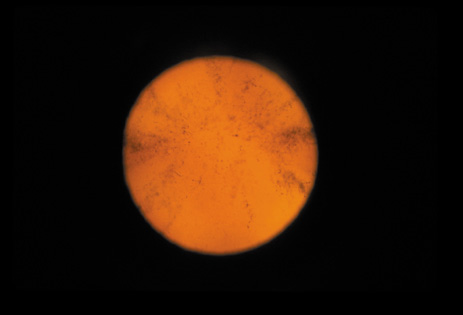

CATARACT ASSOCIATED WITH PRIMARY OCULAR DISEASES

Cataracts can occur secondary to a large number of intraocular diseases. Intraocular inflammation is the most common cause of this type of cataract. These cataracts are typically of the PSC variety. PSCs seen in retinitis pigmentosa (Fig. 31), gyrate atrophy (Fig. 32), and Usher's syndrome (Fig. 33) show finger-like projections. In persistent hyperplastic primary vitreous, the PSC is often associated with abnormal blood vessels from the hyaloid system that arborize from the posterior pole of the lens. Cataracts seen in retinal anoxia and anterior segment necrosis are thought to occur due to interference with the nutrient supplies of the lens. This leads to decreased anabolism, increased catabolism and acidity, and necrosis. The cataracts in these conditions are also of the PSC type. An acute increase in intraocular pressure can cause focal necrosis of the subcapsular epithelium and localized, fleck-like opacities (glaukomflecken). These opacities are initially located immediately under the capsule, but when new fibers are laid down they slowly become buried in the lens. Their presence indicates that the patient has experienced an acute increase in intraocular pressure. The premature occurrence of PSC and possibly nuclear-type cataracts has been noted in eyes with high myopia (Fig. 34).37–41

Fig. 32. PSC in a patient with gyrate atrophy of the choroid and retina. (Courtesy of Muriel Kaiser Kupfer, M.D.).